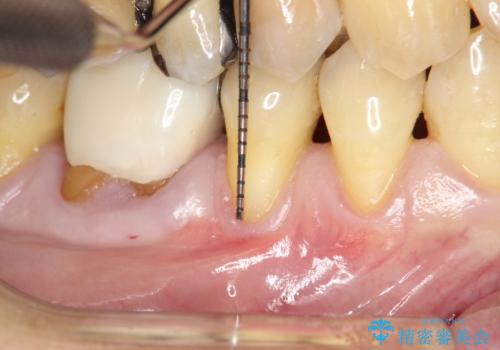

- 右下4番と5番に丈夫な歯肉が不足しているために、徐々に歯肉が下がってきていたケースです。

これ以上の歯肉退縮を防ぐべく、丈夫な歯肉の獲得を目的として結合組織移植術による対応を行いました。

患部にはごくわずかに丈夫な歯肉(角化歯肉)がある状態でした。この丈夫な歯肉の幅を十分に増大させ、厚みを持たせる事で、ブラッシングによっても下がりにくく安定した状態となります。

術式は歯冠側移動術と歯肉結合組織移植術を併用しました。